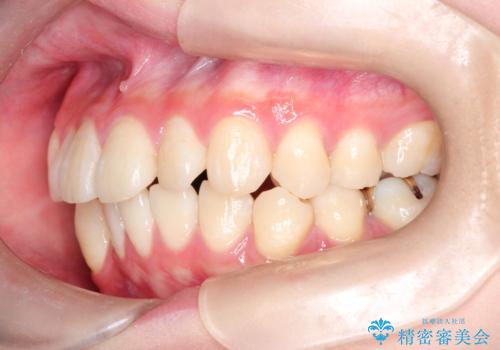

- 上下の前歯に捻れ(捻転)とガタつき(叢生)が見られます。

上の2番目の前歯の捻れに関しては、元々歯の大きさが小さい歯であるため、マウスピースにて力がかかりにくく、捻転の改善が一般的に難しくなりがちです。

下の犬歯に関しても捻れと傾き、ガタつきが大きく、歯根の長さも相まって移動の難易度が高くなりがちです。

インビザラインのそうした特色を踏まえた上で、それらをリカバーできるように治療方式の調整を十分に行い、治療を進めました。

マウスピース枚数 初回33枚 +追加22枚 +追加31枚

概ね2年で治療完了しました。

マウスピース矯正の特性として動かすのが難しい歯を含むケースでしたが、当院独自の工夫を随所に盛り込み、狙い通りの治療結果が得られました。